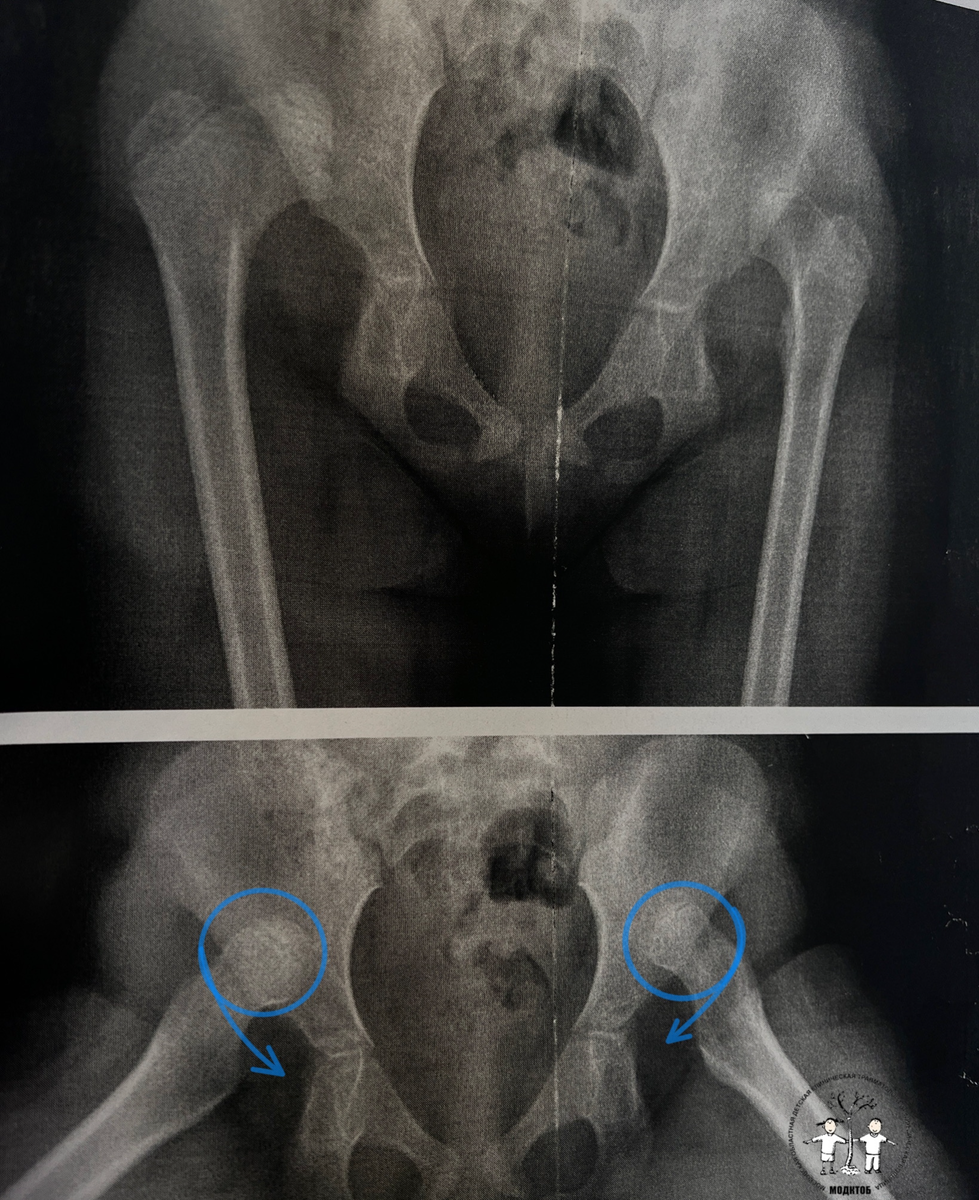

💥При врожденном вывихе тазобедренных суставов кроме неправильной формы элементов сустава возникает полное разобщение суставных поверхностей, головка бедра выходит из суставной впадины и уходит в сторону и вверх.

Двусторонний вывих бедер